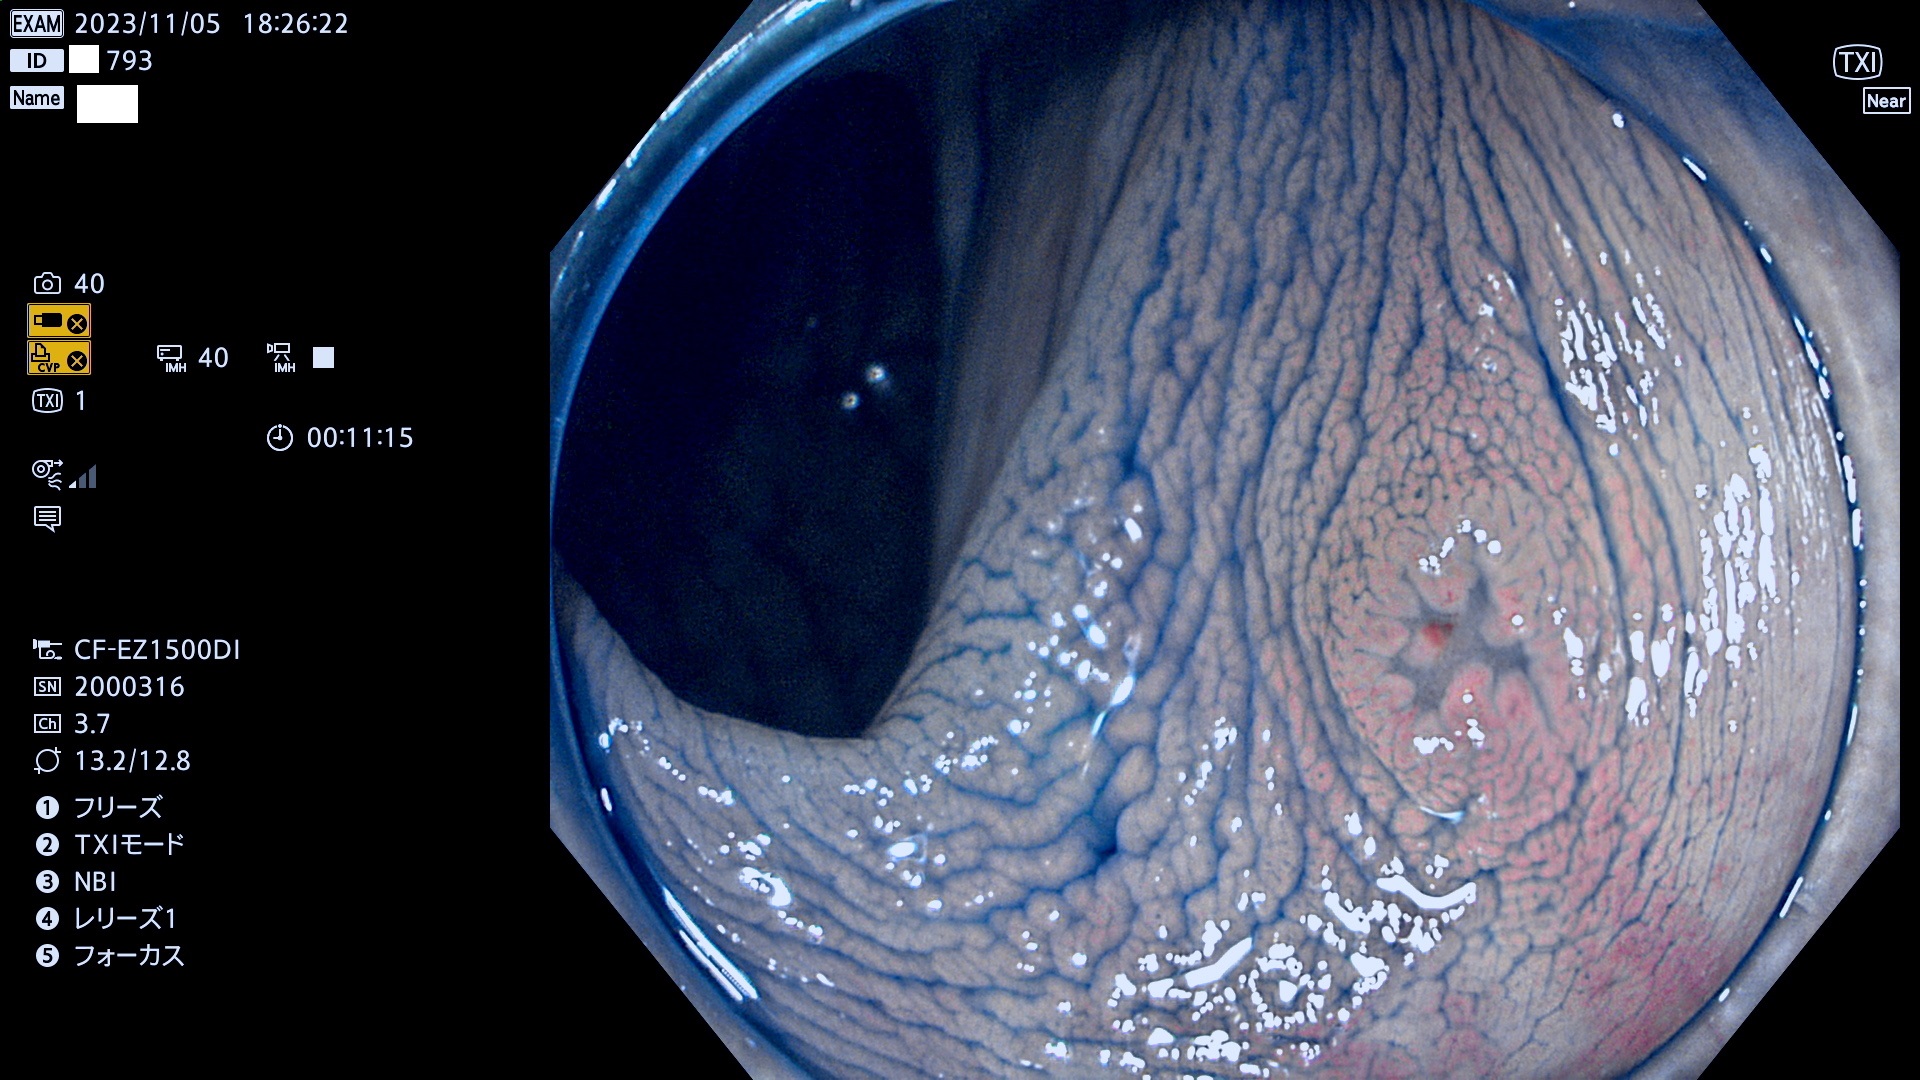

今週のUb、Uc型腺腫

表面型腺腫(Flat Adenoma)の中で、完全に平坦な物をUb、陥凹している物をUcと呼びます。平坦隆起型(Ua)よりも、発見が難しく危険な病変です。このタイプは「内視鏡後・大腸癌の重要犯人」であり、この発見率は「腺腫発見率」よりも、重要な意味があります。

毎週の検査(木・金・土・日)に発見されたUb、Uc型・腺腫を、その週の日曜の夜にUPし1週間、提示します。

抽出の対象期間 2023年11月2日(木)〜11月6(月)の5日間(60件の検査)11件